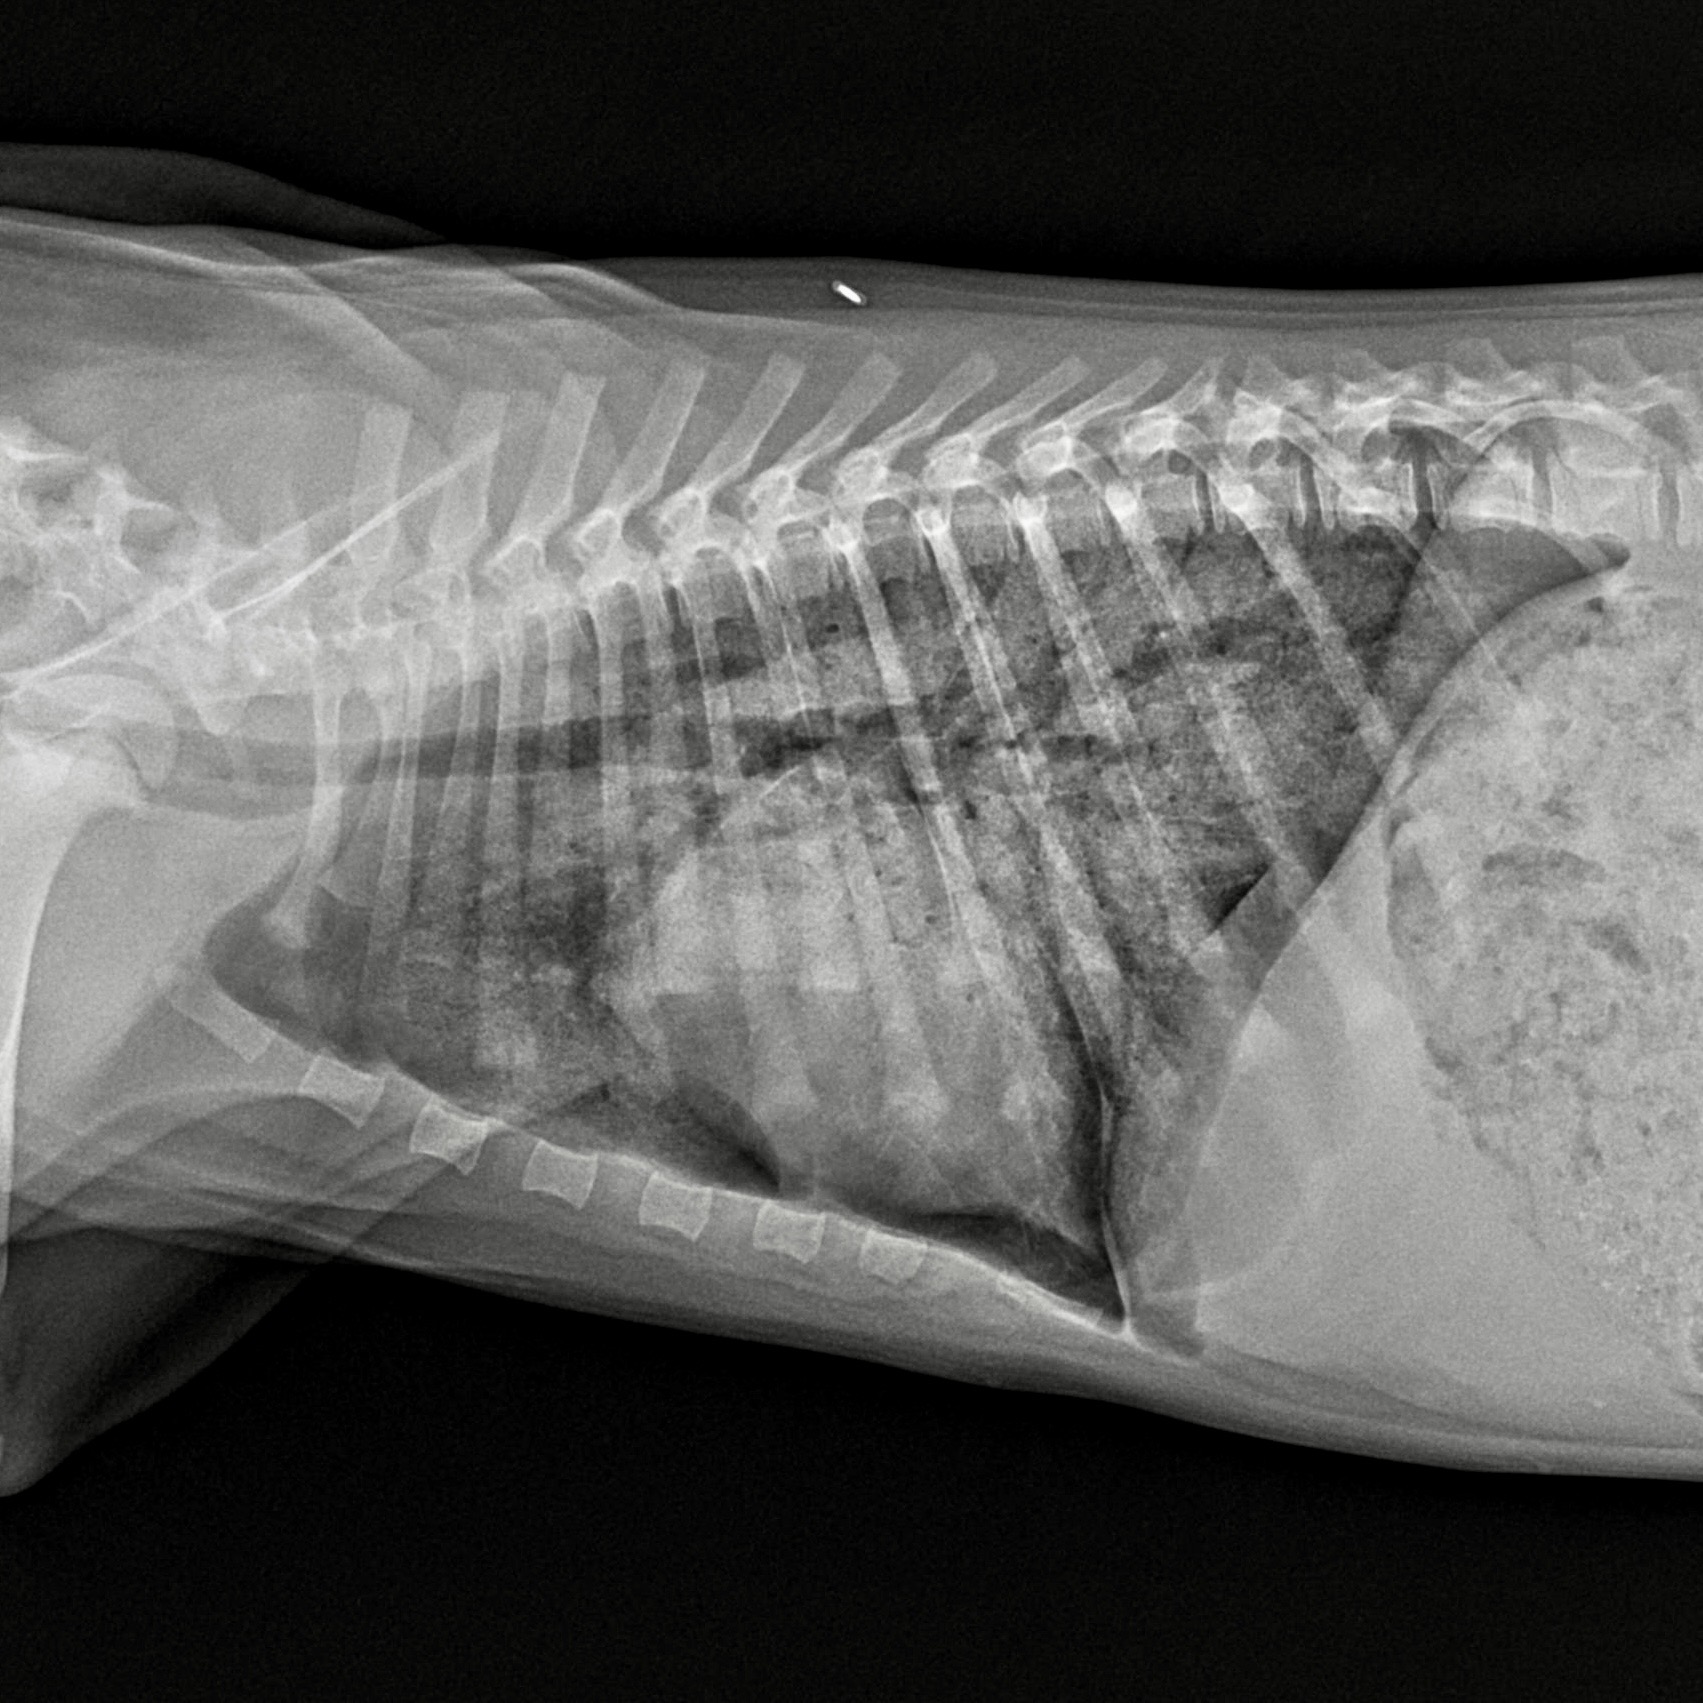

Thoracic radiography

Radiographs typically show:

- Interstitial to alveolar infiltrates

- Perihilar or caudodorsal distribution (variable)

- Normal cardiac silhouette in most cases

Radiographs help confirm pulmonary edema and identify aspiration or traumatic injury.